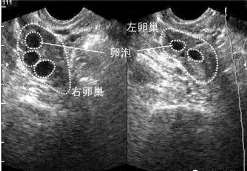

查看全文拉萨卵泡少用什么方案做试管最好,网上助孕工具可信吗 怀孕是一个非常复杂的生理过程,涉及的因素也很多。做试管婴儿 […]